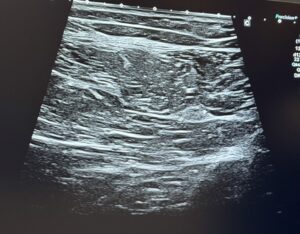

大腿二頭筋短頭の確認方法

プローブを外側に移動し遠位(下方)へ動かすと、大腿二頭筋長頭の外側に「大腿二頭筋短頭」が現れます。

この筋肉は長頭とは異なり、骨盤には付着せず、大腿骨から起始する点で区別されます。

内側ハムストリングスの確認方法

基本ビューからプローブを内側にスライドさせていくと以下の構造が観察されます。

半腱様筋の内側に白く写る:半膜様筋腱

さらに内側:半膜様筋の筋腹

これらの筋や腱は、特にダッシュやキック、急な方向転換などハムストリングスに大きな負荷がかかる動作で損傷を起こしやすい部位となっています。